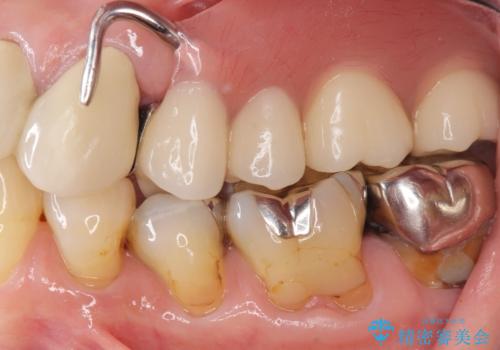

- 上の奥歯がないまま長年過ごしていたら前歯もぐらぐらしてきてしまったことを主訴に来院された患者様です。

奥歯の咬み合わせがないことにより前歯に負担がかかり動揺が出ていました。

精査したところ右下の奥歯も歯周病により保存不可能な状態でした。

なるべく予算を抑えたいとのご希望から、上顎は入れ歯、右下臼歯部はインプラントによる治療を行いました。

上の前歯は動揺を抑え、入れ歯の着脱にも耐えうるように被せ物を連結させることにしました。